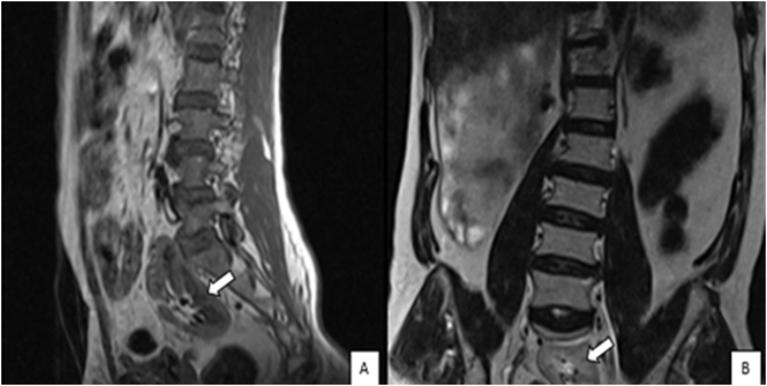

腰椎间盘磁共振成像期间腰椎的偶然椎体外发现。

Incidental extraspinal findings in the lumbar spine during magnetic resonance imaging of intervertebral discs.

To calculate the frequencies of incidental extraspinal findings and incidentally detected congenital anomalies or anatomical differences in the lumbar spine on magnetic resonance imaging (MRI) scans of intervertebral discs.

Of the 379(100%) patients, 90(23.7%) patients were presented with incidental findings. Among the incidental findings, 39(10.3%) were renal cysts, 10(2.6%) were retroverted uteri, 5(1.3%) were Nabothian cysts, 4(1.1%) were ovarian cysts, 10(2.6%) were uterine fibroids, 3(0.8%) were endometrial thickening, 11(2.9%) were indicative of hydronephrosis, 4(1.1%) were uncovered prostatic enlargement, 2(0.5%) were atrophic kidney, and 1(0.3%) each was of an ectopic kidney and bladder wall thickening, respectively.

计算在椎间盘磁共振成像(MRI)扫描中偶然发现的脊柱外异常以及偶然检测到的腰椎先天性异常或解剖差异的发生率。

379例(100%)患者中,90例(23.7%)有偶然发现。在这些偶然发现中,肾囊肿39例(10.3%),子宫后倾10例(2.6%),宫颈纳氏囊肿5例(1.3%),卵巢囊肿4例(1.1%),子宫肌瘤10例(2.6%),子宫内膜增厚3例(0.8%),肾积水11例(2.9%),前列腺增生4例(1.1%),肾萎缩2例(0.5%),异位肾和膀胱壁增厚各1例(0.3%)。